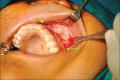

Juvenile nasopharyngeal angiofibroma (JNA) is a rare benign tumor arising predominantly in the nasopharynx of adolescent males. It is an aggressive neoplasm and shows a propensity for destructive local spread often extending to the base of the skull and into the cranium. Clinically, however, it is obscure with painless, progressive unilateral nasal obstruction being the common presenting symptom with or without epistaxis and rhinorrhea. Diagnosis of JNA is made by complete history, clinical examination, radiography, nasal endoscopy and by using specialized imaging techniques such as arteriography, computer tomography and magnetic resonance imaging. Histopathology reveals a fibrocellular stroma with spindle cells and haphazard arrangement of collagen interspersed with an irregular vascular pattern. A case report of JNA with rare intra-oral manifestation in a 17-year-old male patient is presented in the article. JNA being an aggressive tumor may recur posttreatment. Thus, early diagnosis, accurate staging, and adequate treatment are essential in the management of this lesion.